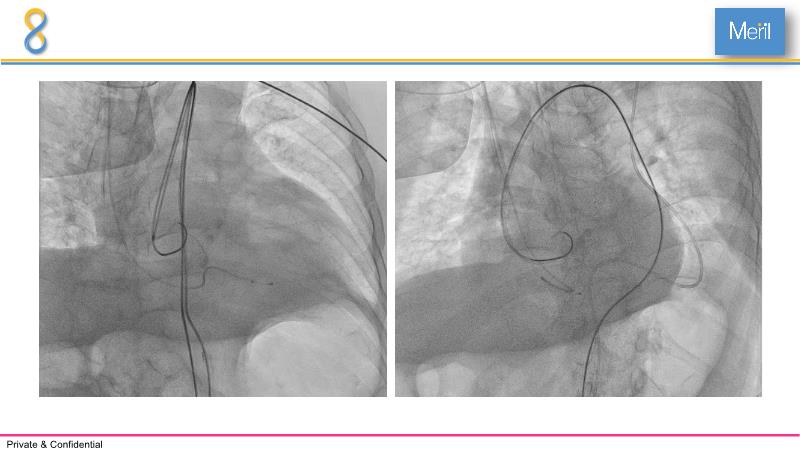

Through the presentation of several compelling cases, including an 88-year-old male with CKD, RBBB, moderate LV dysfunction, and severe aortic stenosis, a Type 1a bicuspid native AS, and an extraordinary TAVI in an 83-year-old with acute heart failure and comorbidities, this session will dive into the Myval Octapro THV. Learn about its key features, procedural impact, and potential clinical benefits. Discover the Octalign technique for predictable and precise commissural and coronary alignment, preserving coronary access. Gain insights into precise sizing, positioning, and deployment of the Myval THV series in real-world scenarios, and explore the relevance of pivotal Landmark RCTs in clinical practice.

- To know the Octalign technique which enables predictable and precise commissural and coronary alignment thus preserving coronary access

- To understand the technique of precise sizing, positioning and deployment of Myval THV series in real world clinical scenarios